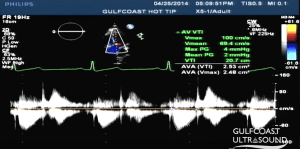

- Aortic valve area (AVA) requires LVOT diameter (D) and velocity time integral (VTI) at LVOT and AV in the continuity equation

- More reliable than CW doppler peak velocity

- Obtain the following in apical view at the aortic valve as parallel to flow as possible to avoid falsely low values

- AV VTI (continuous wave doppler), gate at tips of AV opening in systole, tracing below the line in systole

- LVOT VTI (pulse wave doppler), gate in LVOT just apical to AV, tracing below the line in systole

AVA Continuity Equation

LVOT Diameter (D) in cm

LVOT VTI in cm

AV VTI in cm